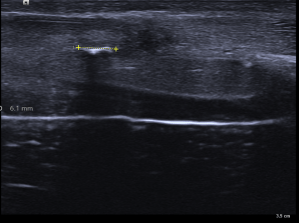

333.Revisión patología testicular. El Varicocele. Tipos y Clasificación.

Son venas del plexo pampiforme de aspecto tortuoso y dilatadas por encima de los 2 mm.

Varicolece. Maniobra de Valsalva.

Medida superior a 2 mm. Grado 1.

Clasificación basado en el diámetro venoso del plexo pampiniforme (en reposo):

Grado 1: Entre 2,5 y 4 mm

Grado 2: Entre 4 y 5 mm

Grado 3: Mas de 5 mm

Estas medidas son de una de las clasificaciones que se usan para el estudio del varicocele. Hay alguna otra de la que hablaremos más adelante, pero esta me parece sencilla para comprender esta habitual figura patológica.

Estas medidas son en reposo y aumentan con la maniobra de valsalva. Ojo.

Existe aumento de flujo con la maniobra de Valsalva como puedes ver en el vídeo.